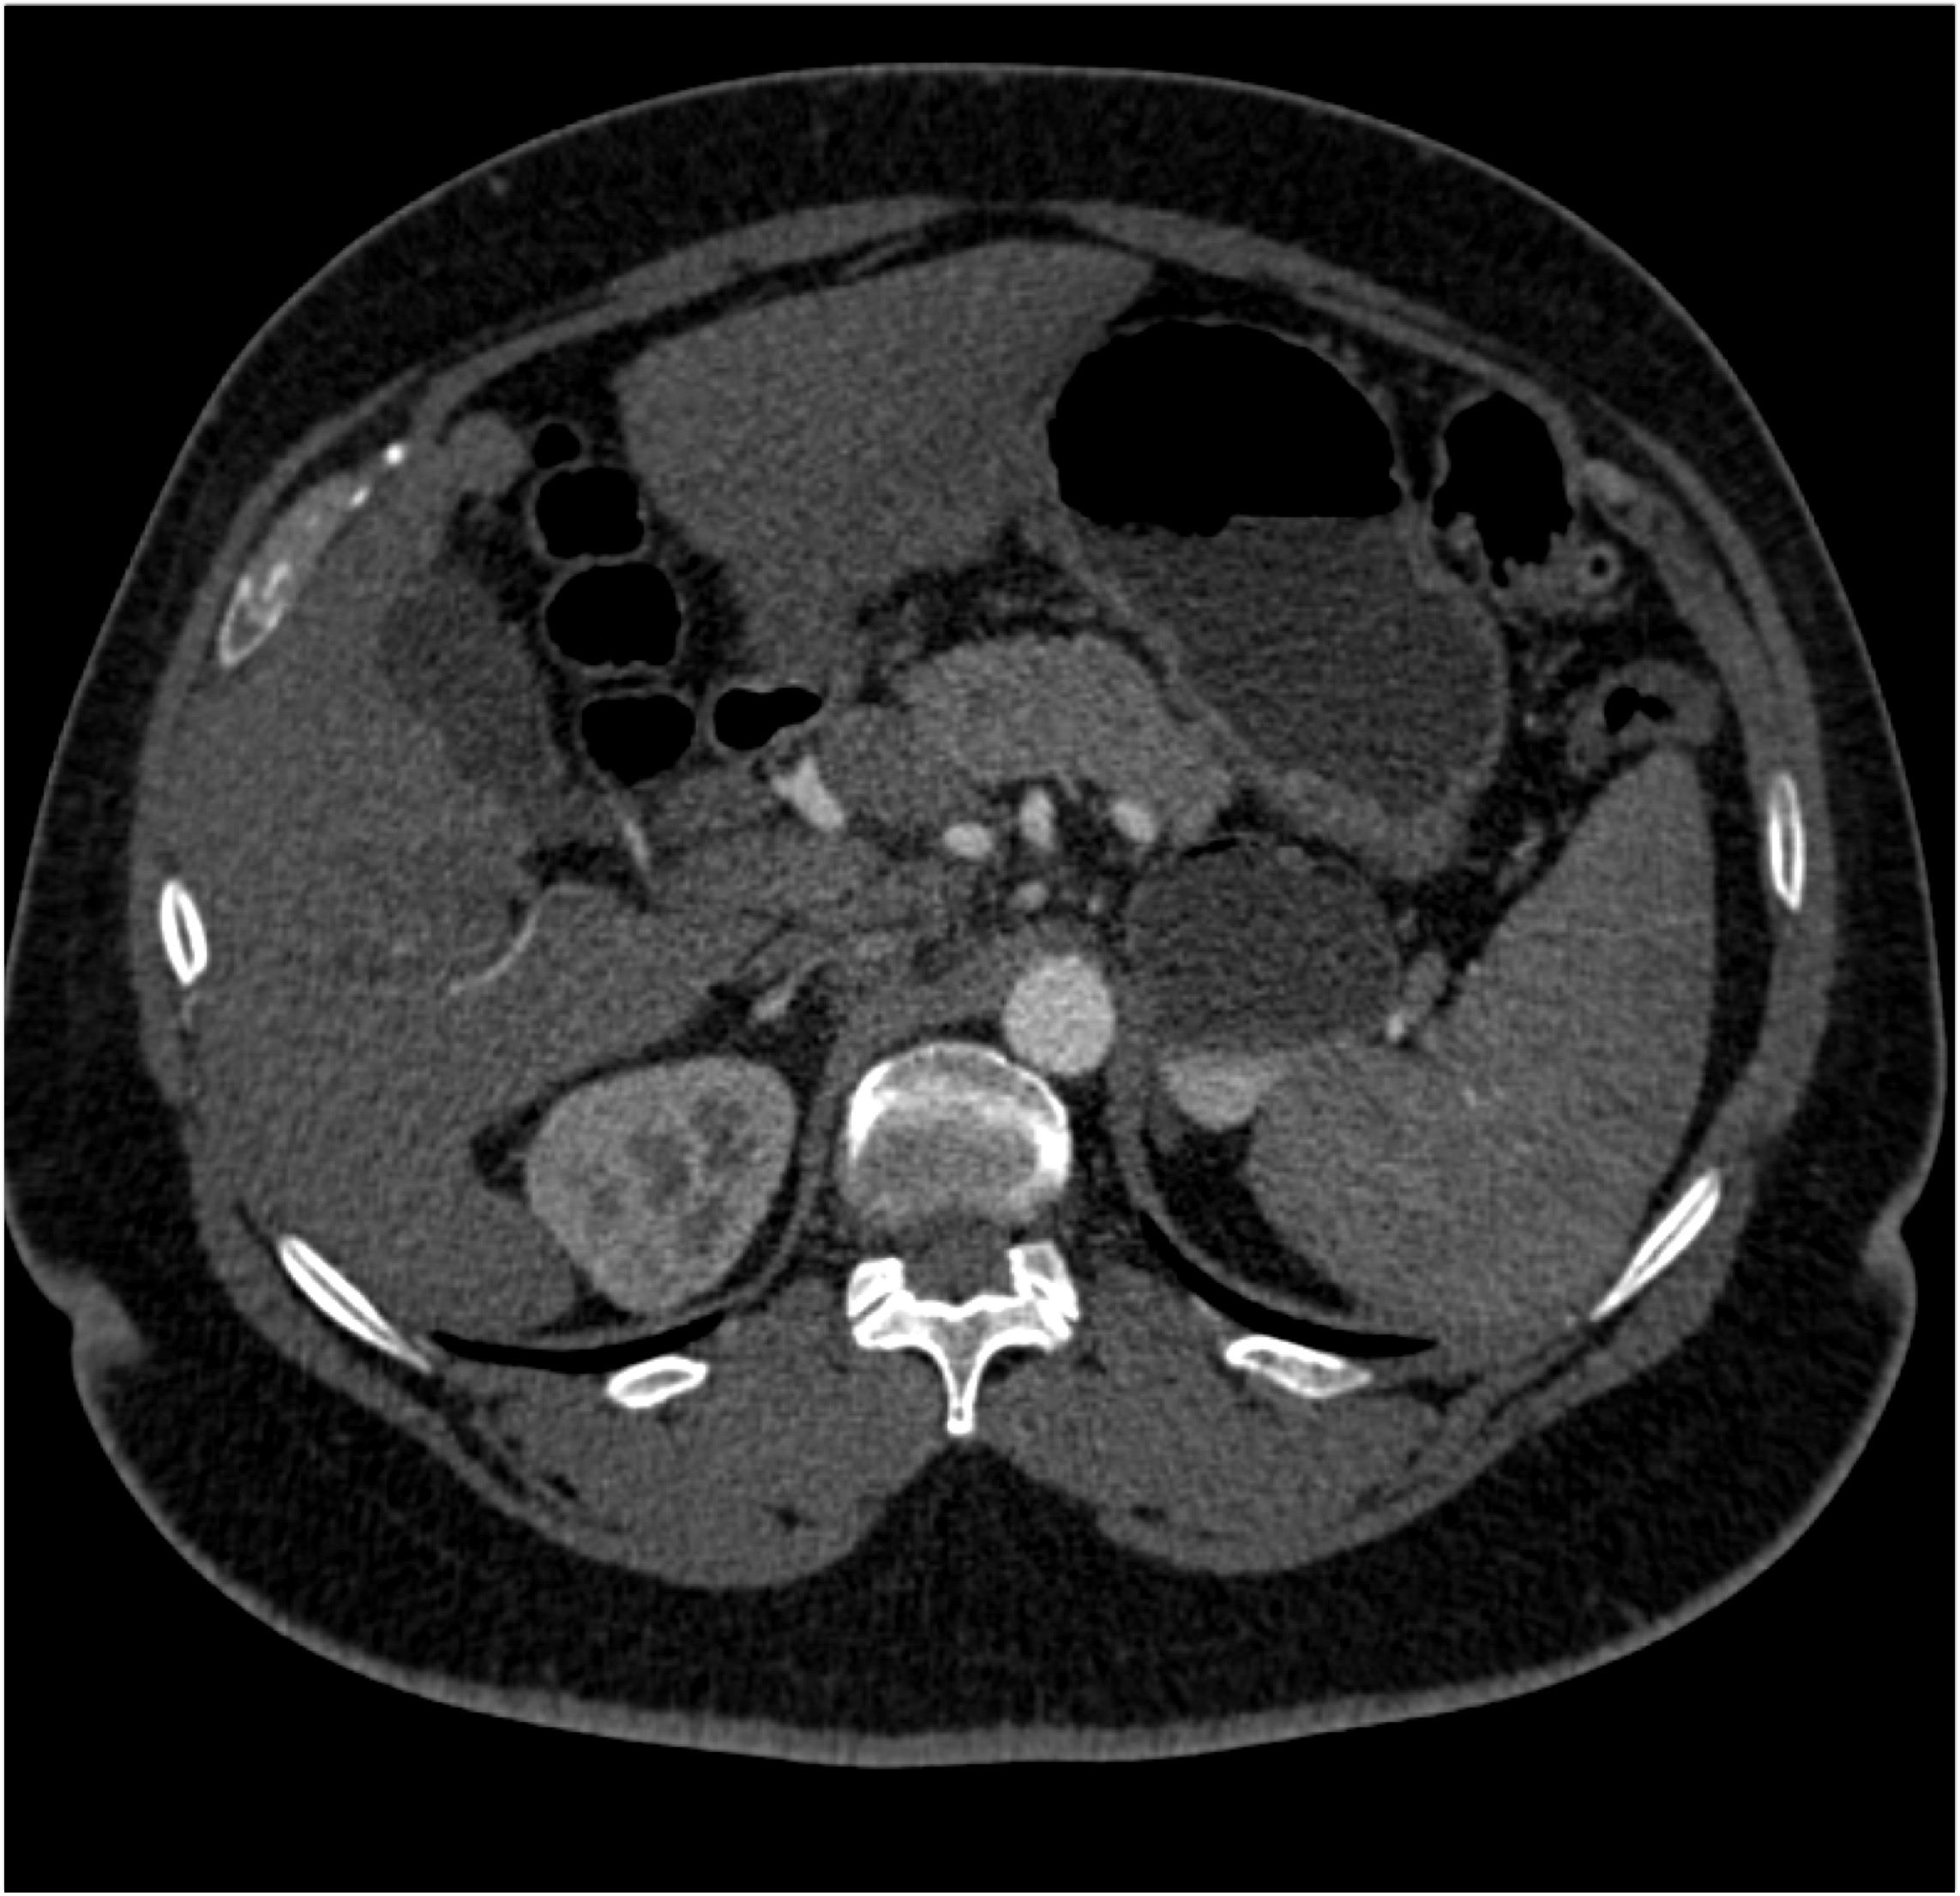

8) In this patient with RUQ pain and no history of trauma the best diagnosis is?

multiple hemangiomas

focal nodular hyperplasia

hepatic adenomas

angiosarcoma of the liver